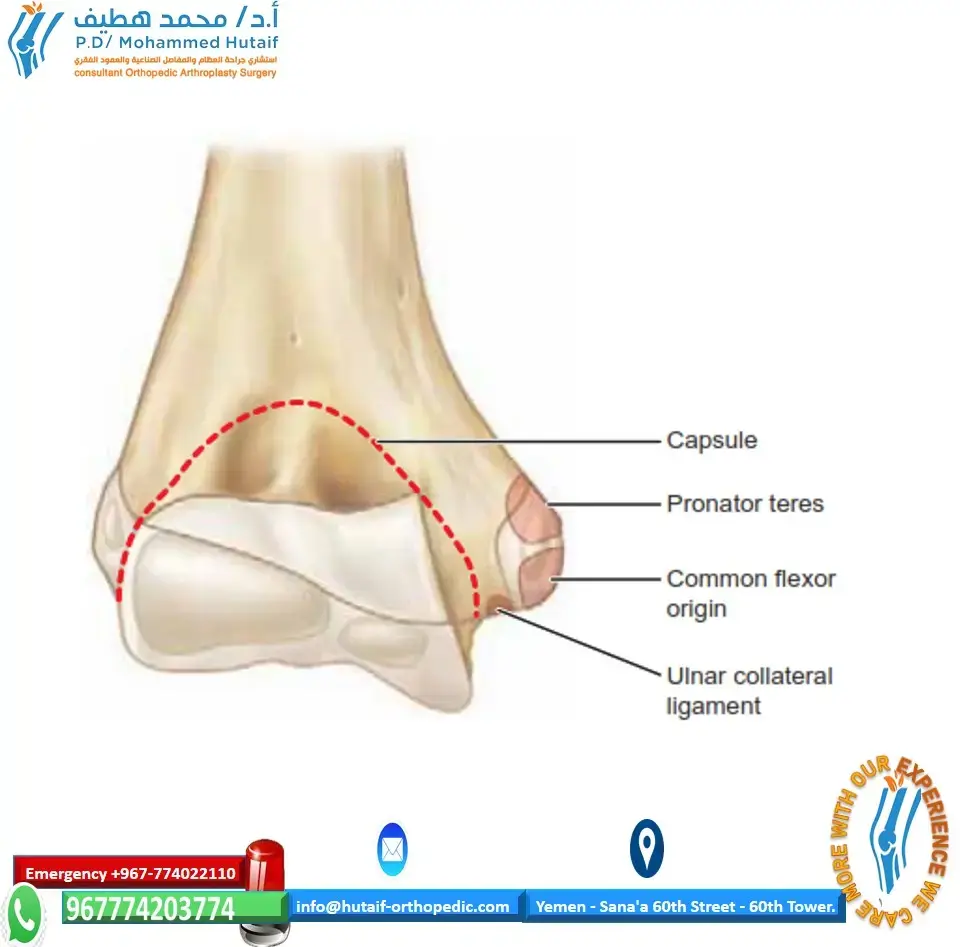

فهم التشريح المعقد والدقيق لمفصل الكاحل

لإدراك أهمية وعبقرية جراحة تثبيت الكاحل، يجب أولاً الغوص في التفاصيل التشريحية لهذا المفصل الحيوي. مفصل الكاحل (المفصل الظنبوبي-القدمي أو Talocrural Joint) ليس مجرد مفصل بسيط، بل هو تحفة هندسية بيولوجية مصممة لتحمل وزن الجسم بالكامل وتوزيع القوى الديناميكية أثناء المشي والجري والقفز.

المكونات العظمية الرئيسية لمفصل الكاحل

يتكون مفصل الكاحل من التقاء ثلاثة عظام رئيسية تعمل بتناغم تام:

- عظم الظنبوب (Tibia): هو العظم الأكبر في الساق ويتحمل الجزء الأكبر من وزن الجسم (حوالي 85-90%). السطح السفلي لهذا العظم يُعرف باسم "سقف الظنبوب" (Tibial Plafond)، وهو السطح الذي يرتكز مباشرة على عظم الكاحل. يمتد الجزء الداخلي من الظنبوب للأسفل ليشكل الكعب الإنسي (Medial Malleolus)، والذي يوفر الاستقرار الجانبي الداخلي للمفصل.

- عظم الشظية (Fibula): هو العظم الأصغر والأرفع في الساق، ويقع في الجهة الخارجية. يمتد طرفه السفلي ليشكل الكعب الوحشي (Lateral Malleolus). رغم أنه لا يتحمل سوى جزء بسيط من الوزن، إلا أن دوره حاسم في توفير الاستقرار الجانبي الخارجي ومنع انزلاق عظم الكاحل للخارج.

- عظم الكاحل (Talus): هو العظم الفريد الذي يربط الساق بالقدم. يتميز بأن حوالي 60% من سطحه مغطى بغضاريف مفصلية ملساء، ولا تتصل به أي عضلات أو أوتار مباشرة، بل يعتمد في حركته واستقراره على الأربطة المحيطة به والتوافق الهندسي مع عظام الساق. السطح العلوي لعظم الكاحل (Trochlea) يكون أعرض من الأمام وأضيق من الخلف، مما يجعل المفصل أكثر استقراراً في وضعية العطف الظهري (Dorsiflexion).

الغضاريف المفصلية والأربطة الداعمة

تُغطى أسطح هذه العظام المتلامسة بطبقة من الغضروف الزجاجي (Hyaline Cartilage)، وهو نسيج أملس ولزج يقلل الاحتكاك إلى أدنى حد ممكن ويمتص الصدمات. في مفصل الكاحل، يكون هذا الغضروف أرق نسبياً مقارنة بمفصل الركبة أو الورك، لكنه يتحمل ضغوطاً هائلة.

إلى جانب العظام والغضاريف، يُحاط المفصل بشبكة معقدة من الأربطة القوية التي تمنع الحركات غير الطبيعية، أبرزها:

* المركب الرباطي الوحشي (Lateral Ligament Complex): يشمل الرباط الشظوي الكاحلي الأمامي (ATFL)، والرباط الشظوي العقبي (CFL)، والرباط الشظوي الكاحلي الخلفي (PTFL). وهي الأربطة الأكثر عرضة للتمزق أثناء التواء الكاحل.

* الرباط الدالي (Deltoid Ligament): رباط قوي جداً يقع في الجهة الداخلية للكاحل.

* المركب المُرتبط (Syndesmosis): مجموعة من الأربطة التي تربط بين عظمي الظنبوب والشظية فوق مفصل الكاحل مباشرة، وتحافظ على تماسك "المدقة" (Mortise) التي تحتضن عظم الكاحل.